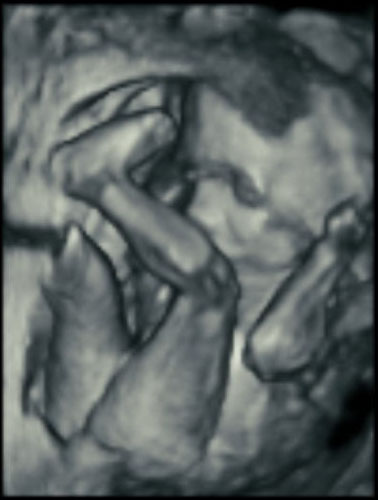

Here’s how ultrasound works in pregnancy: As early as 16 weeks, women can see a “fetal portrait” of their baby and determine its gender. Ultrasound technology has improved dramatically over the decades from flat, grainy black and white images to the current three-dimensional time experience.

Most hospitals offer some 3D scanning, but 3D ultrasound produces images that show the width, height and depth of a developing child. Rather than sending sound waves straight into the womb and recording when they bounce back as is common in 2D imaging, 3D ultrasound sends sound waves from different angles. A computer then renders a 3D image based on this data.

4D ultrasound adds movement as it occurs. The fourth dimension is time. You’re actually watching your baby live in 3D mode. How cool is that?